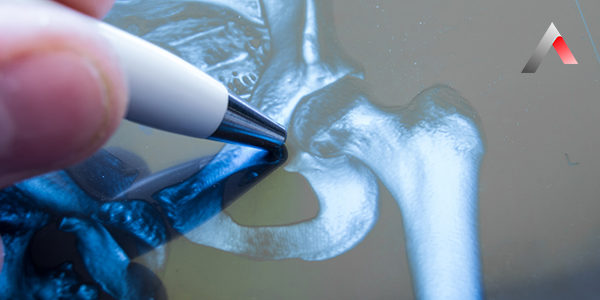

A major joint fracture may require surgical intervention depending on the severity and type of the injury. Surgery generally proceeds through the following stages:

2. Surgical Procedure

During the surgery, local or general anesthesia is usually applied. Repairs can be performed using arthroscopic methods or open surgical procedures. The fracture can be stabilized with screws, plates, or pins.